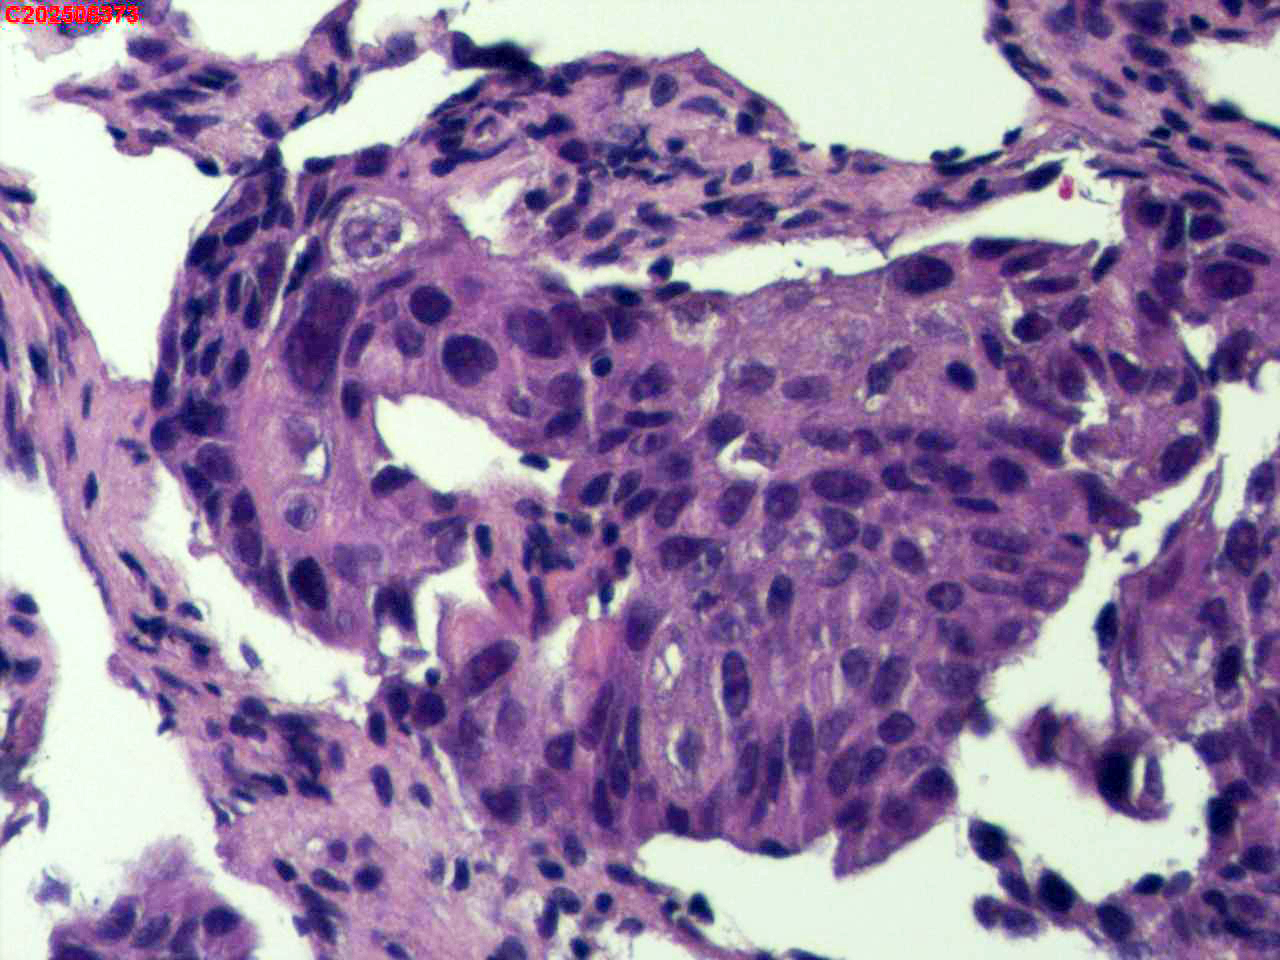

纤支镜咬检

性别

男

年龄

40岁

临床诊断

肺癌?

一般病史

增强CT提示右肺中叶粘液栓;气管镜见右肺中叶外侧段新生物,考虑恶性可能。

标本名称

大体所见

鳞状细胞癌